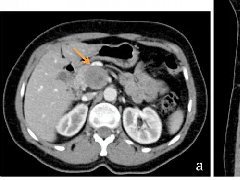

图 1.2 CT 示胰腺头部有一个 35 mm 的低密度病灶,边变界清晰(箭头)。

图 1.3 腹部 CT 增强扫描轴向 (a) 和冠状面 (b) 显示胰头有一个不均匀强化局灶性肿块(箭头)。